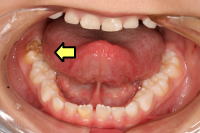

小帯(しょうたい)

上唇や舌のスジで、歯が生える前は歯ぐきの頂点に着いています。そして、歯が生えると歯ぐきから離れていきます。このスジが短いと唇や舌の動きが制限されるため、整形手術が必要なときもあります。詳しくは担当医に相談ください。

上唇小帯(じょうしんしょうたい)

上唇のスジで、短いと唇の動きが制限されます。そのため、おっぱいの吸いが弱かったり、上顎の成長が妨げられて歯ならびが乱れます。また、歯ブラシでこすると痛いので、ご注意ください。